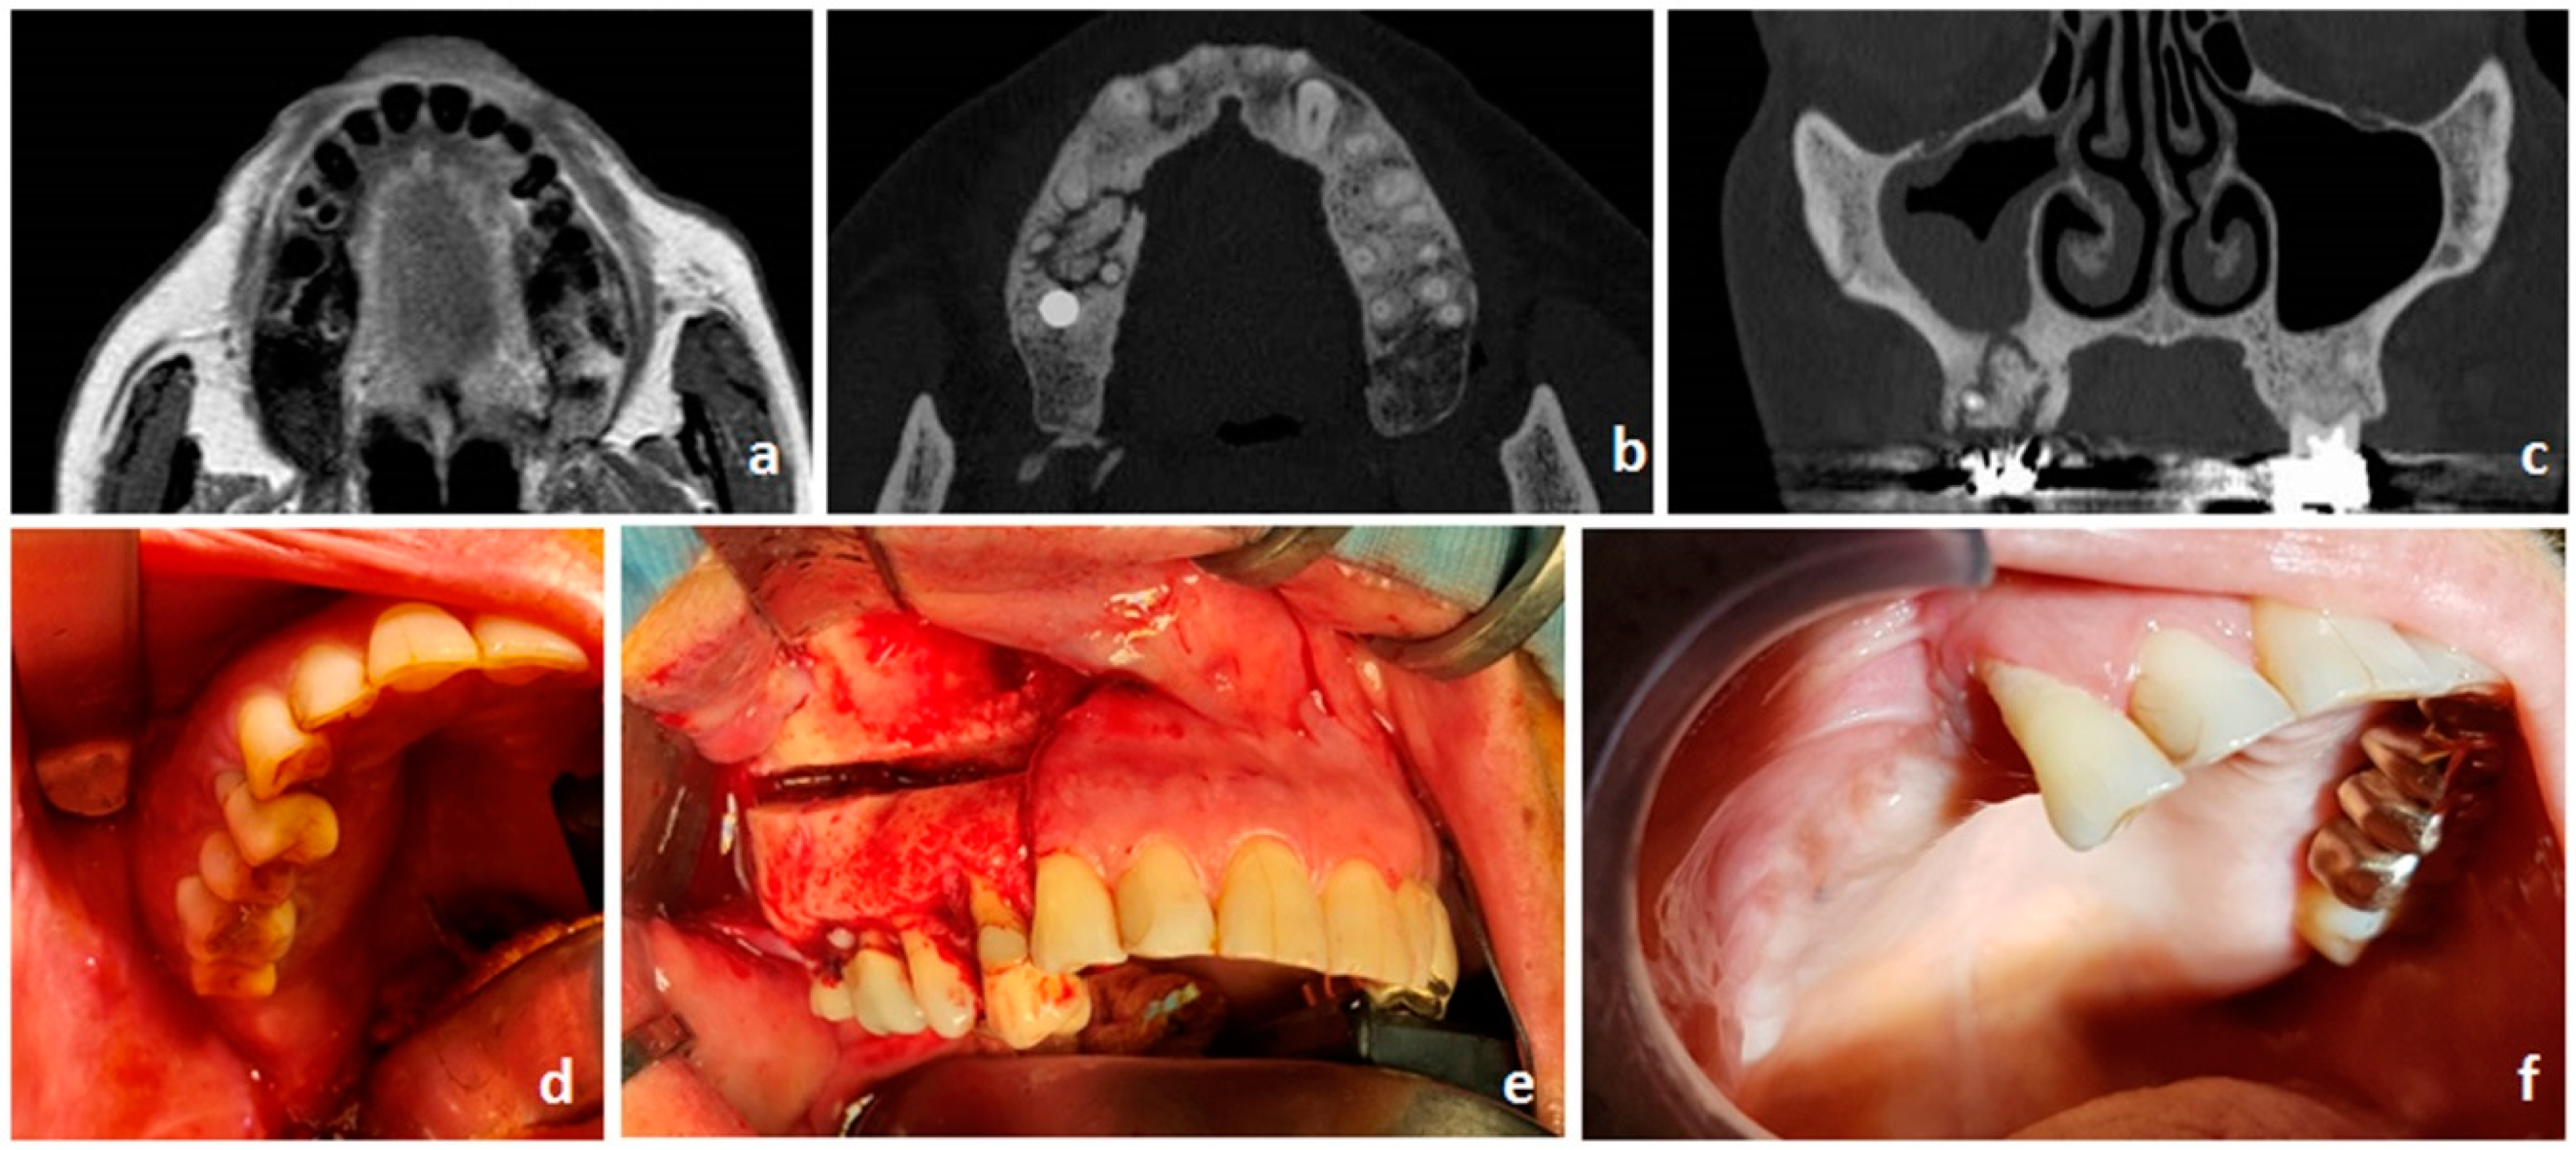

- Bedogni, A.; Blandamura, S.; Lokmic, Z.; Palumbo, C.; Ragazzo, M.; Ferrari, F.; Tregnaghi, A.; Pietrogrande, F.; Procopio, O.; Saia, G.; et al. Bisphosphonate-associated jawbone osteonecrosis: A correlation between imaging techniques and histopathology. Oral Surg. Oral Med. Oral Pathol. Oral Radiol. Endodontol. 2008, 105, 358–364. [Google Scholar] [CrossRef]

- Stockmann, P.; Hinkmann, F.M.; Lell, M.M.; Fenner, M.; Vairaktaris, E.; Neukam, F.-W.; Nkenke, E. Panoramic radiograph, computed tomography or magnetic resonance imaging. Which imaging technique should be preferred in bisphosphonate-associated osteonecrosis of the jaw? A prospective clinical study. Clin. Oral Investig. 2010, 14, 311–317. [Google Scholar] [CrossRef] [PubMed]

- Hutchinson, M.; O’Ryan, F.; Chavez, V.; Lathon, P.V.; Sanchez, G.; Hatcher, D.C.; Indresano, A.T.; Lo, J.C. Radiographic Findings in Bisphosphonate-Treated Patients With Stage 0 Disease in the Absence of Bone Exposure. J. Oral Maxillofac. Surg. 2010, 68, 2232–2240. [Google Scholar] [CrossRef] [PubMed]

- Bedogni, A.; Fedele, S.; Bedogni, G.; Scoletta, M.; Favia, G.; Colella, G.; Agrillo, A.; Bettini, G.; Di Fede, O.; Oteri, G.; et al. Staging of osteonecrosis of the jaw requires computed tomography for accurate definition of the extent of bony disease. Br. J. Oral Maxillofac. Surg. 2014, 52, 603–608. [Google Scholar] [CrossRef] [PubMed]